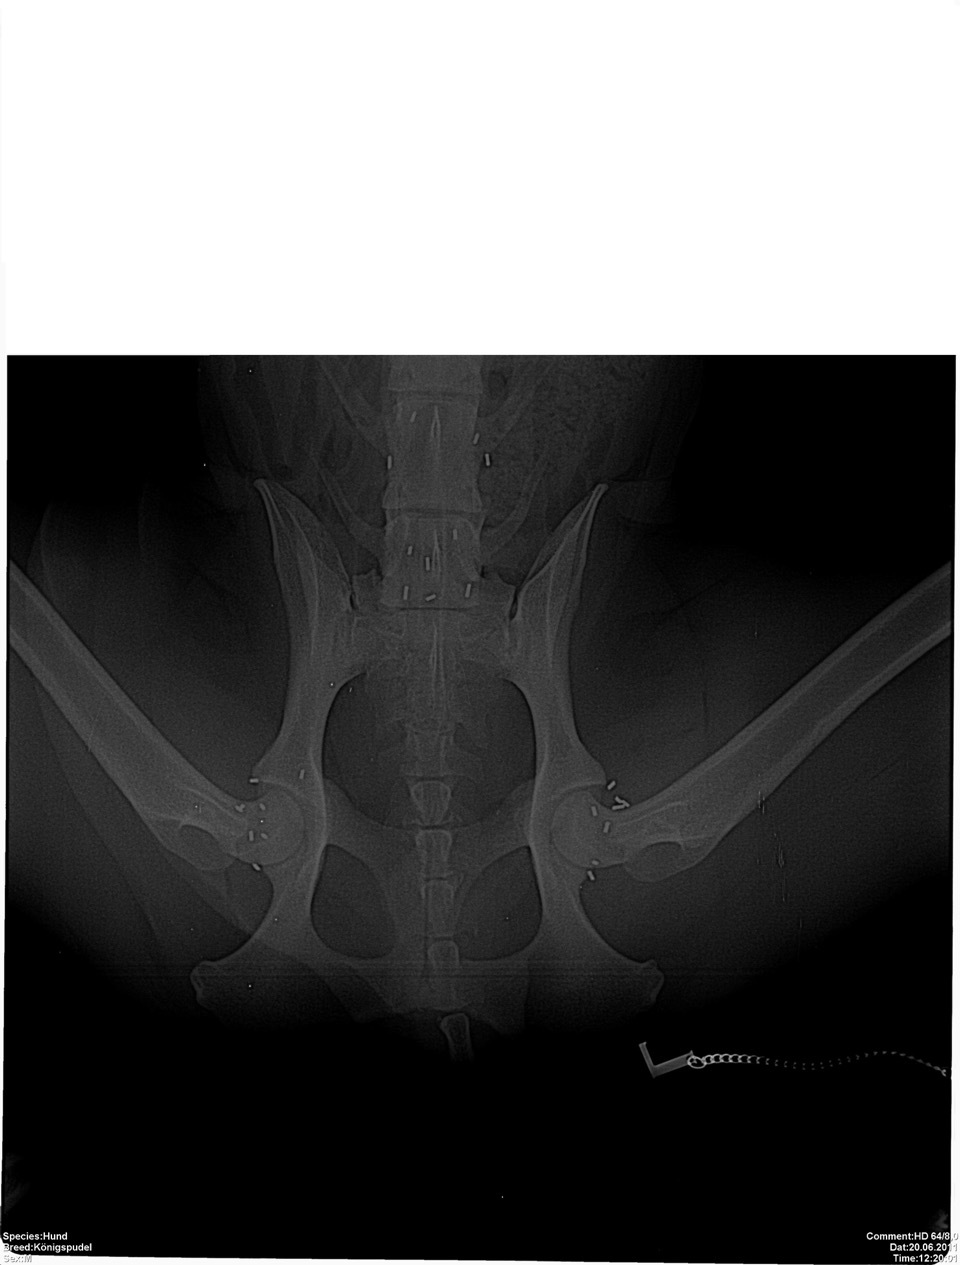

Bei einer eingehenden Lahmheitsuntersuchung fällt besonders der aufgezogene Rücken, sowohl im Stand als auch in der Bewegung, auf. Das für Hüft- und Beckenprobleme charakteristische „Po-Wackeln“ zeigte Tommy schon immer, allerdings hielten seine Besitzer das bisher nicht für ein Krankheitssymptom. Schließlich humpelte er ja bisher nicht. Neben weiteren Auffälligkeiten des Gangbildes ist vor allem der Schwung aus der Hinterhand und die Beweglichkeit der Wirbelsäule deutlich reduziert. Tommy legt sich beim Laufen regelrecht auf die Vorderhand. Beim Abtasten zeigt Tommy Schmerzen im Rücken sowie im Becken- und Hüftbereich. Auch die Triggerpunkte der Ellbogen reagieren auf beiden Seiten schon auf leichten Druck. Der Verdacht auf Arthrose in den Hüft-, Wirbel- und Ellbogengelenken wird  durch anschließende Röntgenbilder bestätigt. Was nun? Arthrose ist nicht heilbar. Also müsste Tommys Frauchen damit rechnen, ihn für den Rest seines Lebens immer wieder wegen Schmerzen behandeln zu lassen.

Bei der Goldimplantation werden dem Patienten nach einer sehr ausführlichen Untersuchung in Sedierung 1-3 Millimeter lange Golddrahtstückchen mittels einer Hohlnadel an Akupunkturpunkte und/oder spezielle lokale Punkte injiziert. Hauptanliegen der Goldimplantation ist die ganzheitliche Therapie des Körpers. Es wird also nicht z.B. eine einzelne Gelenkerkrankung behandelt, sondern die Bewegung als Einheit harmonisiert. Durch die entzündungslindernde Wirkung der Goldimplantate werden durch Entzündungen verursachte Schmerzen gelindert, die Durchblutung in diesem Gebiet verbessert und somit der Stoffwechsel und das Gangbild harmonisiert. Übrigens sind die Goldimplantate kein Hindernis für andere Behandlungsmethoden wie z.B. Akupunktur oder Chirurgie. Sie können sogar im Gegenteil oft sehr gut kombiniert werden. Bei punktgenauer Implantation durch spezialisierte Tierärzte stellt sich in der Regel recht bald eine Schmerzfreiheit oder zumindest –armut ein. Der Patient kann sich wieder besser bewegen und erlangt somit mehr Lebensqualität und Lebensfreude. Vorhandene Arthrosen werden nicht beseitigt, doch durch die Schmerztherapie können Schmerzmedikamente erheblich reduziert oder sogar abgesetzt werden. Da das Gold im Körper nicht abgebaut wird, hält diese Wirkung dauerhaft an.

Tommy bekommt in Narkose Goldimplantate an die zu seiner Problematik (Hüfte, Wirbelsäule und Ellbogen) passenden Akupunkturpunkte und zusätzlich ausgesuchte lokale Punkte. Er bewegt sich bereits wenige Tage nach der Goldimplantation (GI) deutlich lockerer. Schon nach wenigen Wochen sind die Triggerpunkte beim Abtasten nicht mehr sensibilisiert und Tommy spielt wieder fröhlich mit seinen Hundefreunden im Park. Diese Wirkung hält seit inzwischen sieben Jahren dauerhaft an, und Tommy hat viel Freude an seinem speziellen Senioren-Trainingsprogramm.